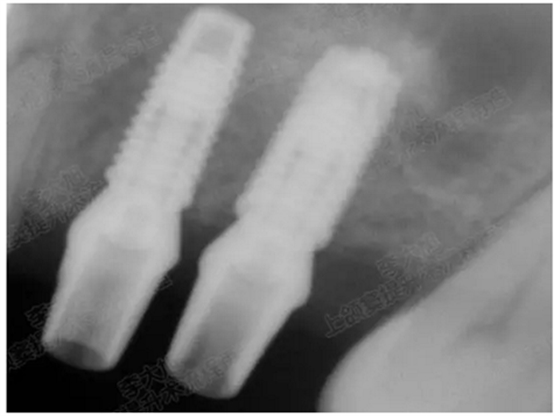

病例二

剩余骨量2mm

003.png

提升10mm